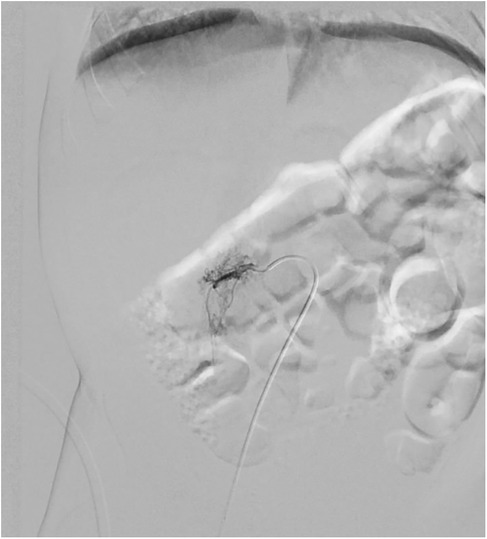

Furthermore, 6 months after embolization, a CT scan revealed that the retroperitoneal mass had significantly shrunk in comparison to previous radiological exams: it measured 30.2 × 14 × 36 mm (a total volume of approximately 7.965 mm3, about 26,2% of the original mass), and it was difficult to determine whether it was still surrounding retroperitoneal vessels (Figure 4).

CT scan images show two different cross-sections of the abdomen. The left image outlines a region with a volume of thirty-two point eight cubic centimeters and an area of seven point nine square centimeters. The right image outlines a smaller region with a volume of three thousand seventy-four point four cubic millimeters and an area of one hundred fifteen point eight square millimeters. Both sections are marked with green boundaries and blue annotations.

Figure 4. On the left abdominal CT scan at admission, on the right abdominal CT scan 6 months after embolization.